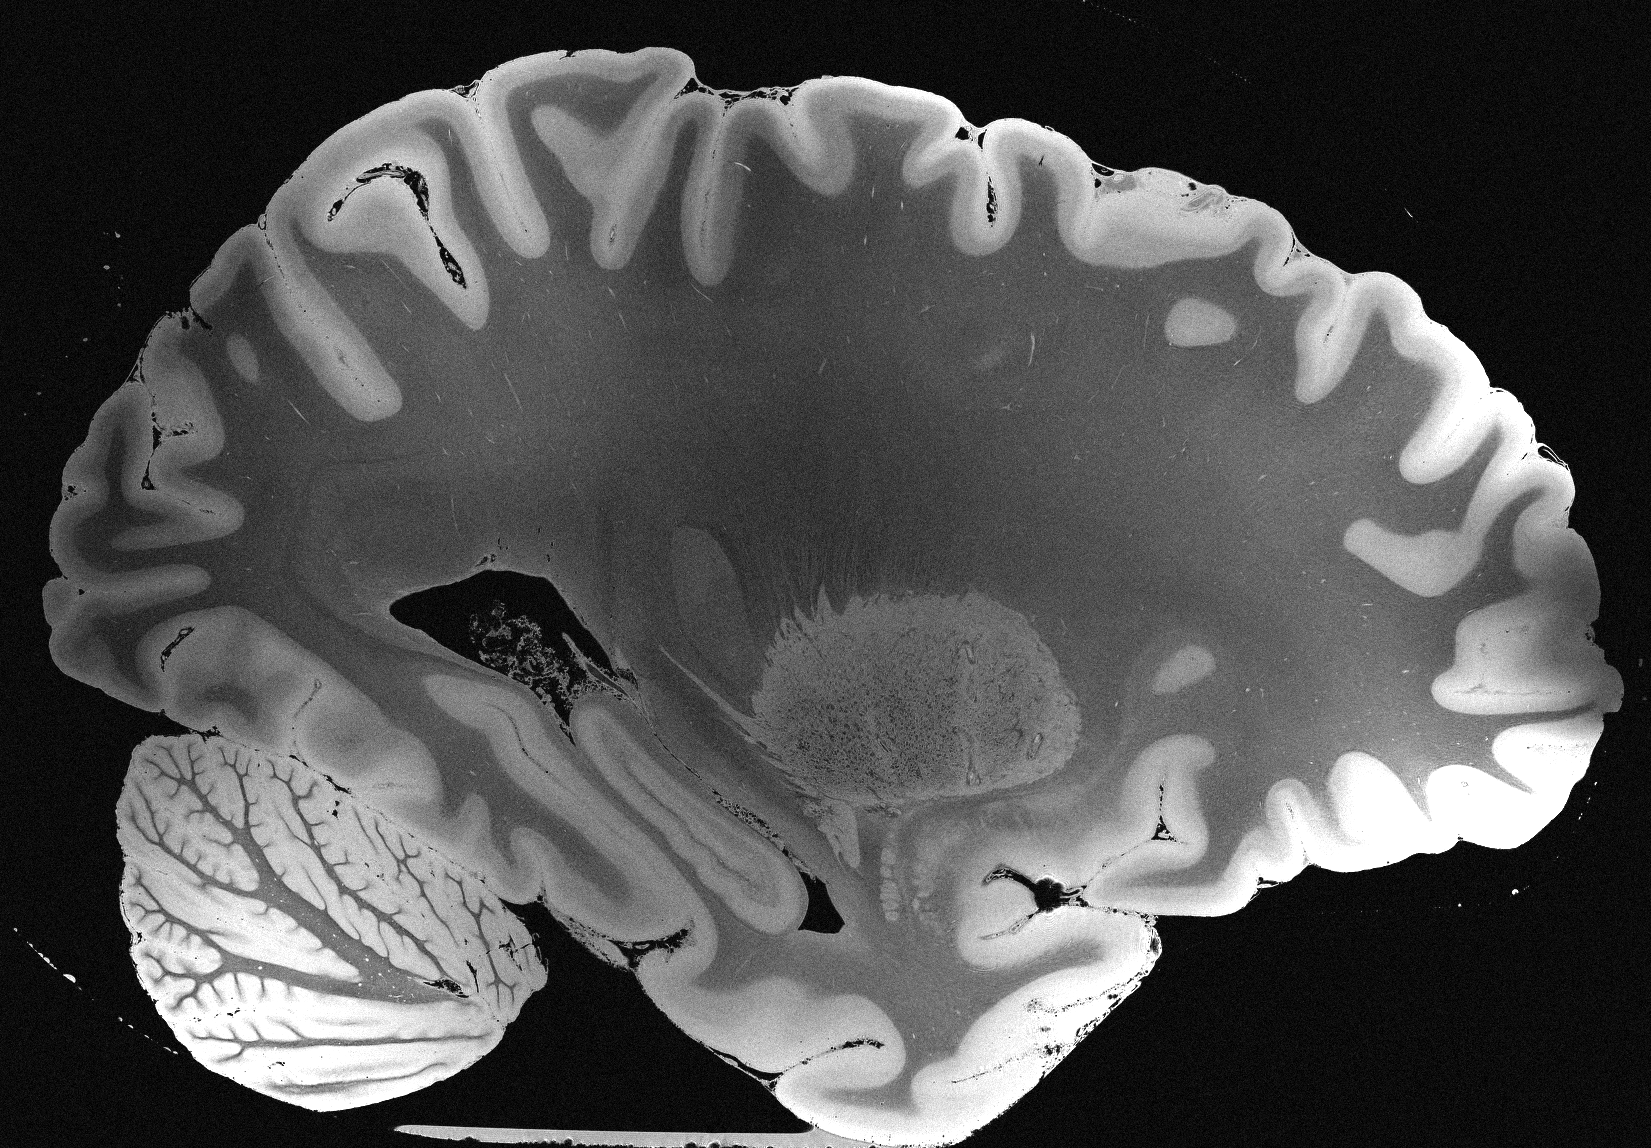

4.2 Registration to a 100 micron ex-vivo brain MRI volume

To showcase the efficacy of our method on real large scale images, we register a 250 in-vivo MRI image (Lüsebrink et al., 2017) to a 100 ex-vivo FLASH human brain volume (Edlow et al., 2019). This represents an inverse problem with more than 11.2B optimizable parameters (compared to 20M for clinical datasets), or 44.8GB of GPU memory. The entire problem does not fit on most GPUs, necessitating distributed multimodal registration. We optimize a composite transform - affine followed by a diffeomorphic mapping; details can be found in Section E.1. Multimodal deformable registration took 58 seconds on 8 NVIDIA A6000 GPUs, which is unprecedented at this resolution. Fig. 6 shows qualitative results, highlighting the ability to register highly detailed structures such as cerebellar white matter; these structures are not visible at macroscopic scales. The resultant advantages of performing registration at this scale can allow researchers to characterize the neuroanatomy at microscopic resolutions and allow morphometric analysis of cortical layers and subcortical nuclei among other structures.